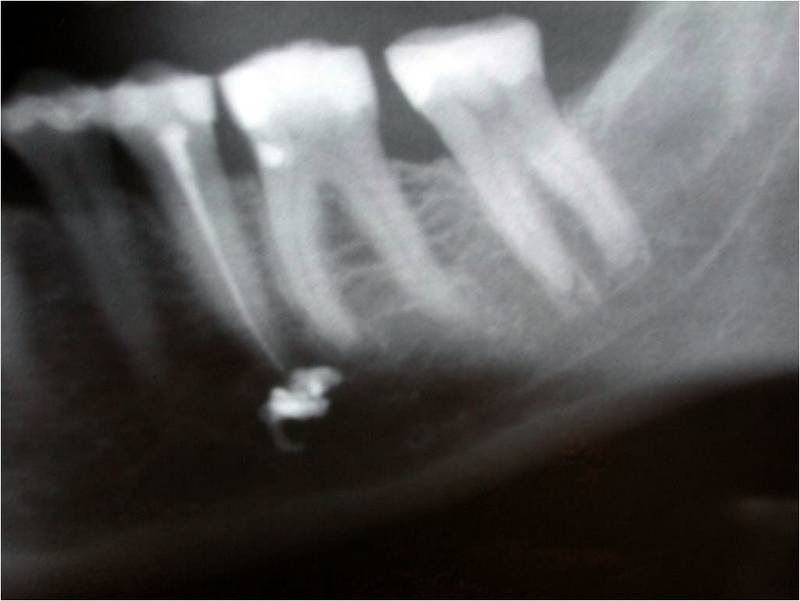

Root Canal Material In The Nerve Canal